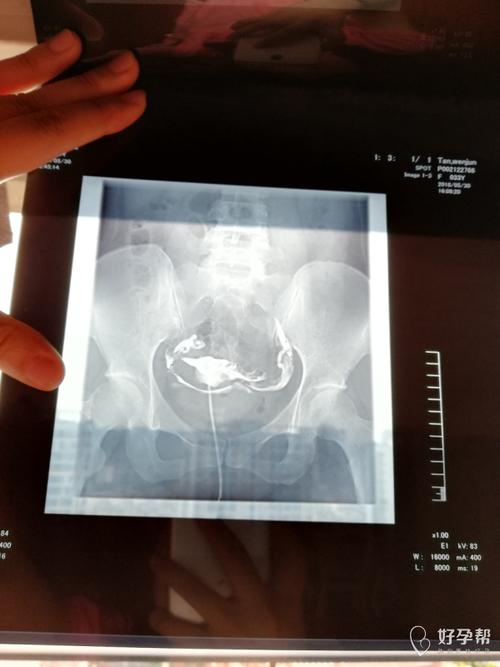

1、输卵管造影是一种传统的检查方式,它使用膀胱截石位,用阴道窥镜的方式对输卵管粘膜进行物理检查,能更直观、快速的了解输卵管粘膜的情况,可检查子宫腔、子宫腔、输卵管、卵巢的恢复情况。而对于有瘢痕组织、坏死组织、积脓、纤维化物,则需要手术治疗。

输卵管造影,顾名思义,是从妇科中通输卵管而使女性的生殖系统恢复正常的生殖功能的一个项目。